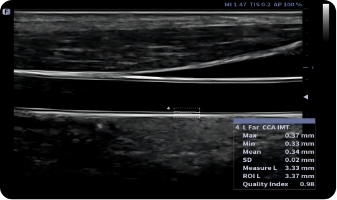

Auto IMT

Mierzenie powierzchni naczynia krwionośnego, prędkość przepływu krwi może być automatycznie mierzona przez spektrum, a wyniki objętości przepływu krwi zostaną wyświetlone.

Obrazy kliniczne